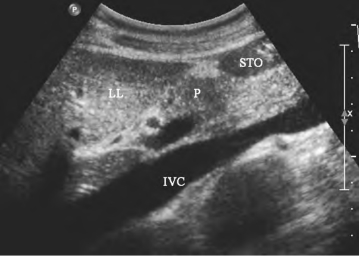

1.36.4四、腹腔大血管